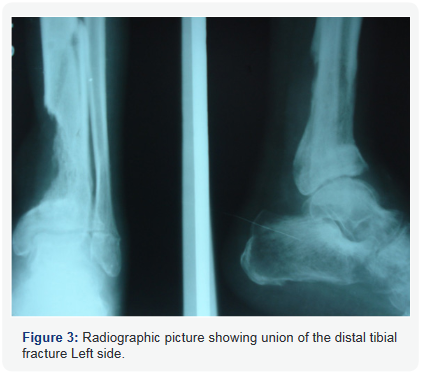

In first stage debridement of wound, removal of fixator and cross leg fasciocutaneous flap over non-healing left leg wound was done and deformity corrected intra operatively by manipulation, maintained using plaster slab. In second stage (4 weeks after first stage) autogenous bone grafting of left distal tibia fracture and tendon transfer of tibialis posterior tendon through interosseous route for right side foot was performed. Figure 2 shows the clinical picture of the patient post stage 1 showing healed fascio cutaneous flap. Figure 3 shows the radiographic picture showing union of the distal tibial fracture Left side.

The tibia fracture non-union got united satisfactorily over a period of 6 months with patient’s left foot maintained in neutral position secondary to posterior release and resulting in a functionally better foot. On right side foot drop was corrected secondary to tibialis posterior tendon transfer with ankle range of movement of 40 degrees after physiotherapy